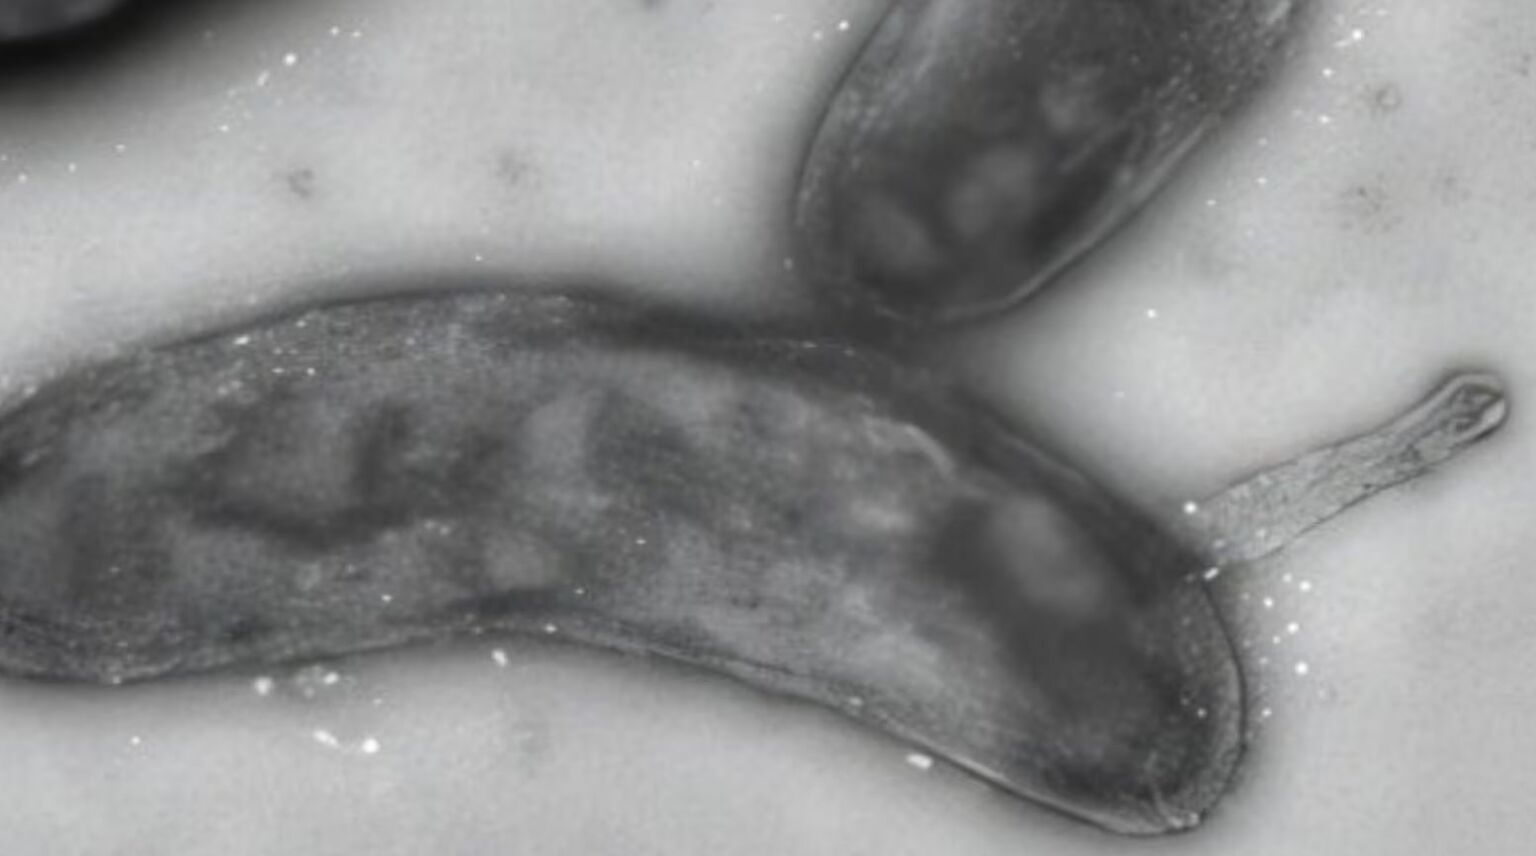

Um menino de três anos em San Antonio, no Texas, Estados Unidos, contraiu gonorreia após ingerir uma placa de laboratório com a bactéria Neisseria gonorrhoeae, segundo relatório médico publicado em 1984. A mãe da criança, técnica de microbiologia, havia deixado o filho no carro enquanto levava compras para casa. Ao retornar, descobriu que ele havia consumido a maior parte do conteúdo de uma cápsula de laboratório, usada para cultivar bactérias em ágar chocolate, substância marrom feita de glóbulos vermelhos.

O caso é incomum porque a gonorreia é geralmente transmitida por contato sexual. Em crianças, infecções da doença costumam levantar suspeitas de abuso sexual, mas neste episódio a contaminação ocorreu de forma acidental, por ingestão de culturas laboratoriais.

Relatórios médicos anteriores já documentaram infecções de técnicos de laboratório com N. gonorrhoeae, mas casos pediátricos por essa via são extremamente raros, uma vez que crianças normalmente não têm acesso a ambientes com culturas da bactéria.